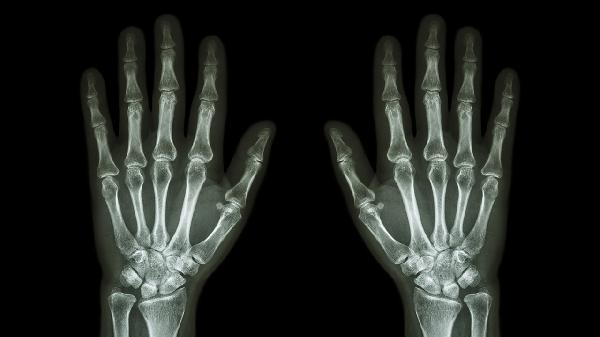

月骨周围脱位主要分为月骨周围背侧脱位、月骨周围掌侧脱位、经舟骨月骨周围脱位和经桡骨茎突月骨周围脱位四种类型。月骨周围脱位通常由高能量外伤导致,可能伴随腕关节肿胀、疼痛及活动受限等症状,需通过影像学检查确诊。

月骨周围背侧脱位是月骨相对于周围腕骨向背侧移位,常由腕关节过伸性损伤引起。患者可能出现腕部剧烈疼痛、背侧肿胀及握力下降。X线检查可见月骨与头状骨对位异常。治疗需在麻醉下进行闭合复位,并用石膏固定4-6周,若复位失败或合并骨折则需手术切开复位内固定。